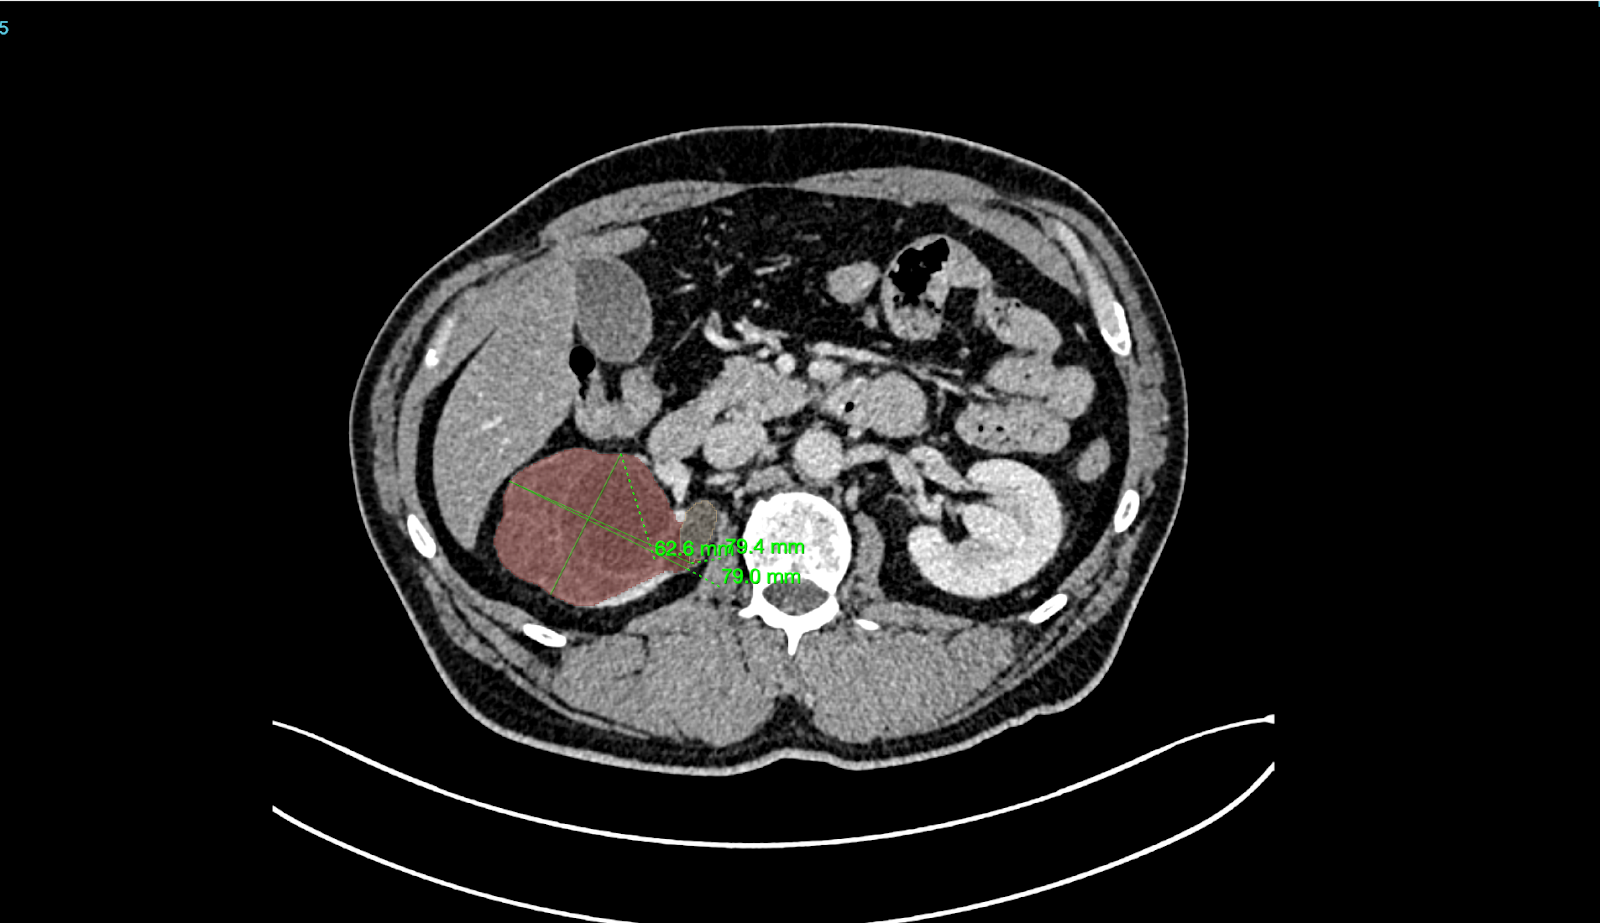

Better Medicine provides an AI-powered radiology solution, BMVision Kidney, designed to enhance diagnostic consistency and speed in kidney cancer detection. It is the first and only CE-certified AI model specifically trained to identify renal tumours from CT scans.

The software runs fully on-premise within UMC’s infrastructure, integrates with existing PACS and viewer systems, and processes CT data in standard formats to deliver interpretable results. Using advanced deep learning, BMVision Kidney automatically detects, segments, and characterises kidney lesions—including incidental findings—with accuracy comparable to radiologists. The solution strengthens diagnostic reliability, reduces variability, and supports faster, more consistent clinical decision-making within UMC’s radiology workflow.